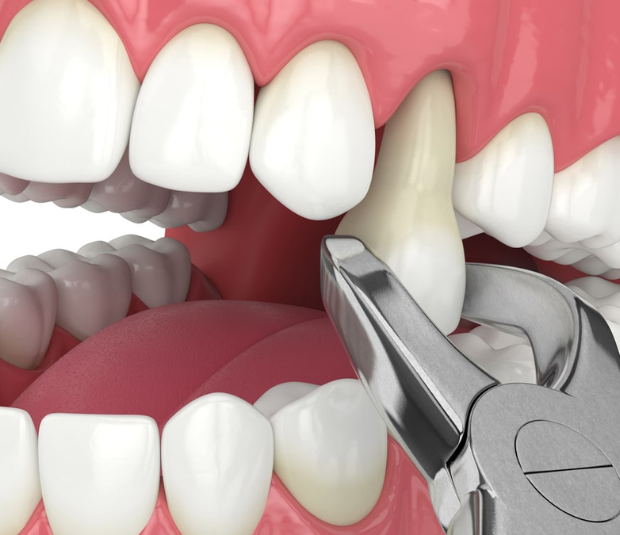

Tooth Extraction

🔹 Simple Extraction – Performed on visible teeth using local anesthesia.

🔹 Surgical Extraction – Required for impacted, broken, or deep-rooted teeth.

✅ Gentle & Precise Extraction – Using advanced tools for minimal trauma.